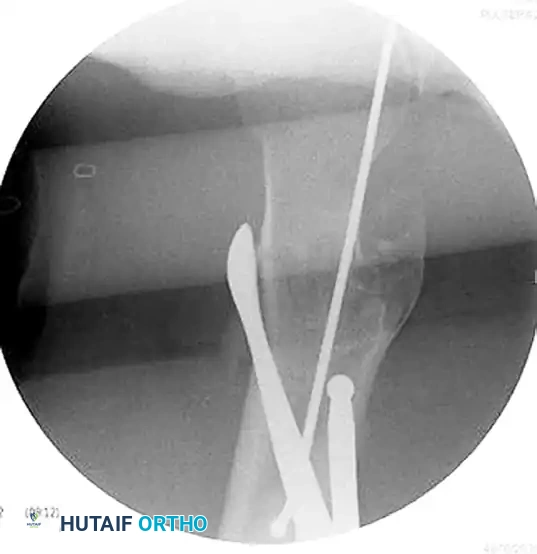

Figure D: Intraoperative lateral fluoroscopic image demonstrating the correction of the sagittal plane deformity using the same reduction aids.